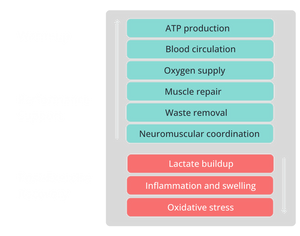

Red light stimulates mitochondria to boost adenosine triphosphate (ATP) production, providing essential energy for cell repair and regeneration. This accelerates recovery from muscle fatigue, enhances cellular renewal, and improves skin vitality.

Red light lowers pro-inflammatory cytokines like TNF-α and boosts antioxidant defenses, reducing oxidative damage. It effectively alleviates arthritis pain, post-surgical swelling, and skin inflammation, such as acne and eczema.

Red light enhances nitric oxide (NO) release, improving oxygen delivery and waste removal through better circulation. It relieves diabetic circulation issues, varicose vein symptoms, and cold extremities, while aiding recovery in athletes.